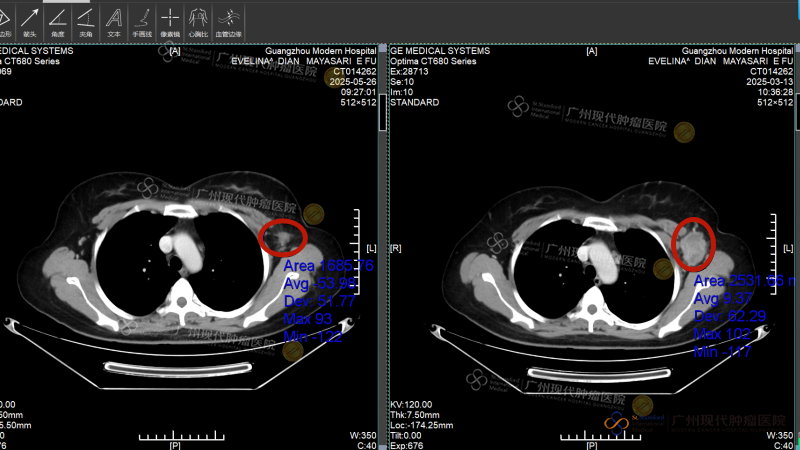

Empat minggu kemudian, Intervensi kedua benar-benar membawa keajaiban: Tumor metastasis di hati menyusut dari 16cm menjadi sekitar 2 cm, asites menghilang, dan fungsi hati perlahan kembali normal. Pemeriksaan pencitraan ulang menunjukkan: benjolan di payudara dan lesi di hati menyusut drastis, sebagian bahkan mengalami nekrosis. Saat Evelina mengambil foto liburan di pinggir jalan Guangzhou dan mengirimkannya kepada teman-teman di kampung halamannya, balasan yang ia terima semuanya sama:“Kamu yakin diagnosisnya tidak salah? Ini tidak terlihat seperti pasien kanker!”

Sebelum pengobatan, tumor hati berukuran sekitar 16cm; setelah pengobatan, tumornya telah kehilangan aktivitas